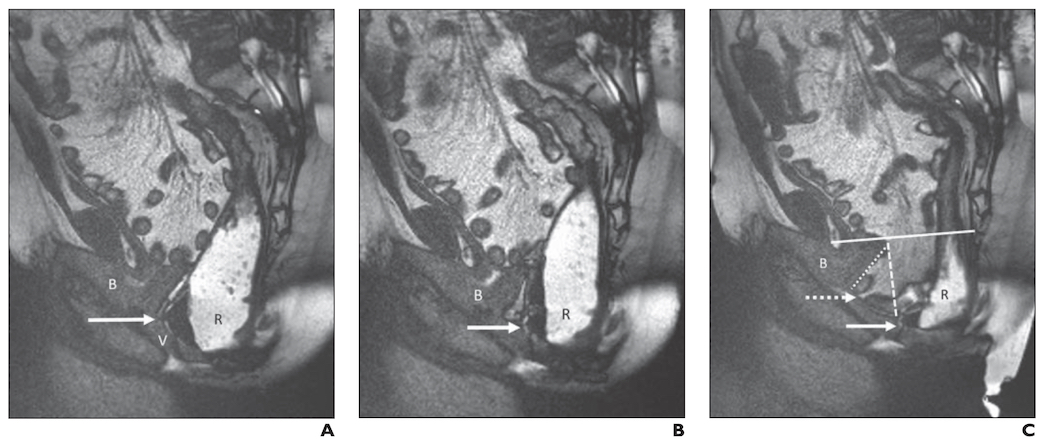

Dans un article de l'American Journal of Roentgenology (AJR) approuvé par plusieurs sociétés (publié en même temps que Diseases of the Colon & Rectum, International Urogynecological Journal et Female Pelvic Medicine and Reconstructive Surgery Journal), les 24 membres du groupe de travail du PFDC sur l'IRM sont parvenus à un consensus, concernant de nombreuses considérations cliniquement pertinentes pour la réalisation, l'interprétation et le compte rendu de la défécographie par résonance magnétique. Sur la base des directives consensuelles du groupe de travail PFDC sur l'IRM, des modèles d'interprétation synoptique correspondants ont été suggérés pour cette population de patients.

Les modèles et les techniques décrits dans cet article de l'AJR peuvent être complétés par des manœuvres radiologiques supplémentaires et des éléments de contexte - indications spécifiques au patient, préférences des prestataires de soins de santé, modèles de pratique locaux, etc. – « mais les recommandations et les étapes cliniques que cet article produit doivent être exigées comme un prérequis lors de la réalisation et de l'interprétation de la défécographie par IRM chez les patients présentant des troubles d'évacuation du plancher pelvien », ont conclu les 15 coauteurs de cet article.